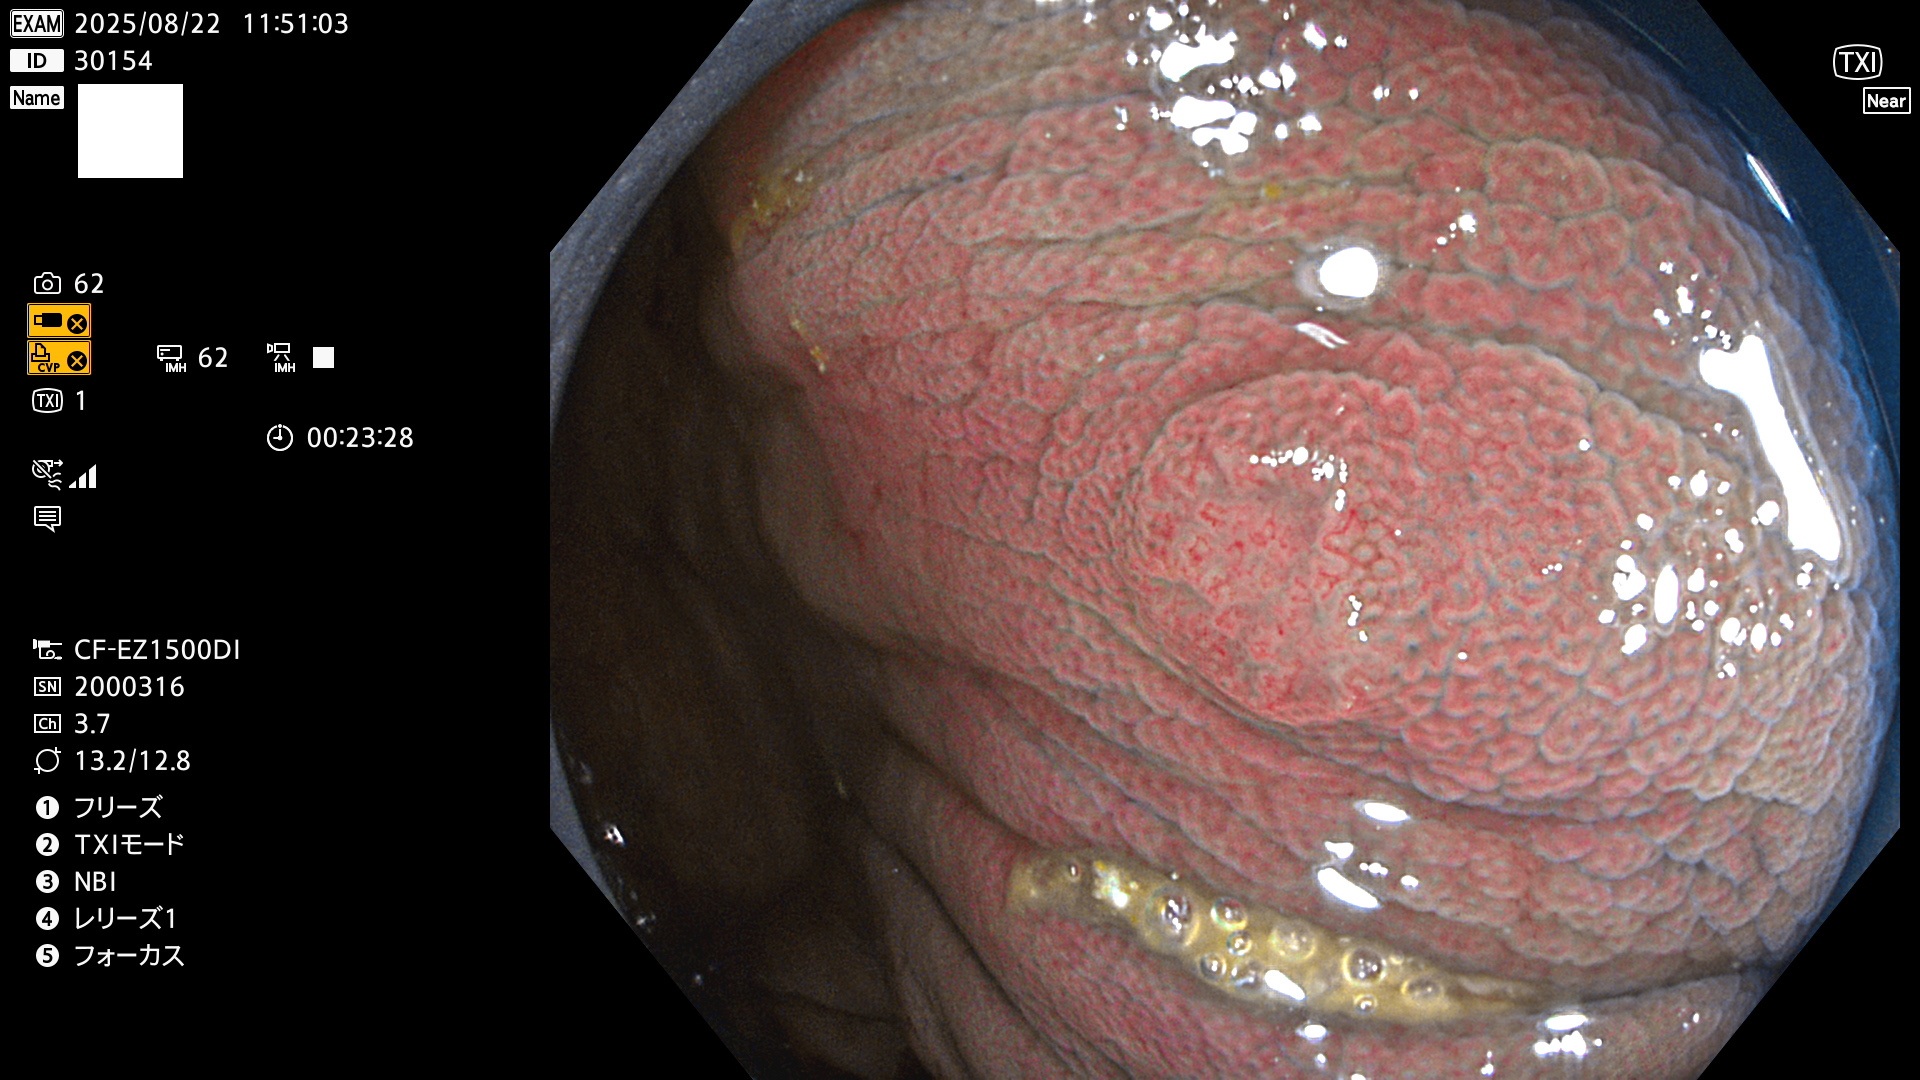

完全に平坦な物をUb、陥凹している物をUcと呼びます。Ubは認識が困難で、Ucはびらん(炎症)と紛らわしいために見落とされやすく、「内視鏡後・大腸癌」の原因になります。

毎週の検査(木・金・土・日)に発見されたUbとUc型・腺腫を、その週の日曜の夜にUPし1週間、提示します。

2025年8月21日〜8月24日の4日間(30件)5個 (Uc_ADR=3個/35人=14%)